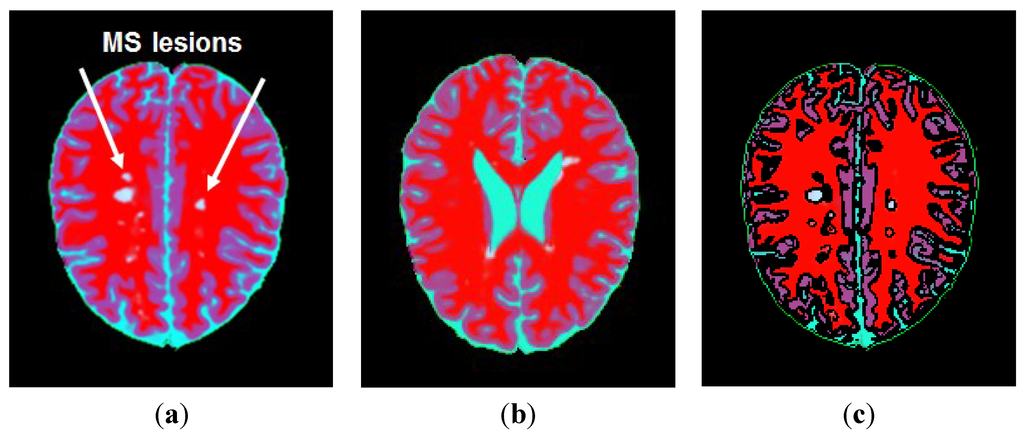

3.1. Segmentation of MS Lesions in a Slice

3.1.1. Estimation of Pseudo-Color Tissue Intensity Averages via IJM Image Segmentation

3.1.2. Contrast Equalization via a Pseudo-Grayscale Conversion